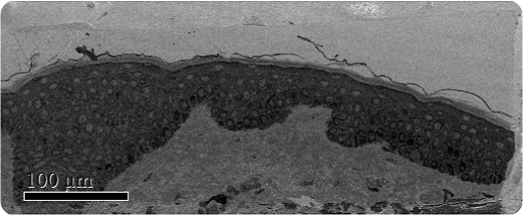

Low magnification SBFSEM image

Figure 1. Low magnification SBFSEM image displaying the entire block-face sample with a field of view of 200 x 500μm.